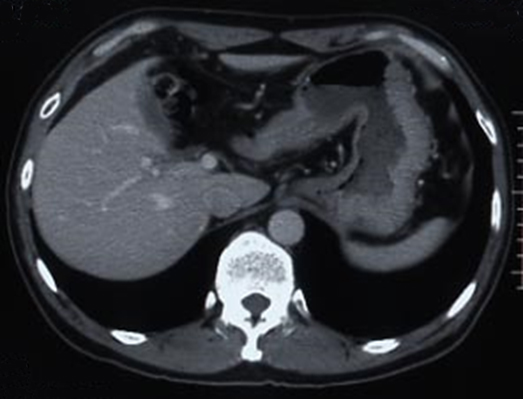

腹部造影CT所見:食道および胃周囲の静脈拡張は明らかでなかった.腫大リンパ節,遠隔臓器転移,腹水は認めなかった.また,肝臓・脾臓にも異常は認めなかった(Fig. 3).

CT findings: Tumor and lymph node swelling was not clear. No abnormality was found in the liver and spleen.